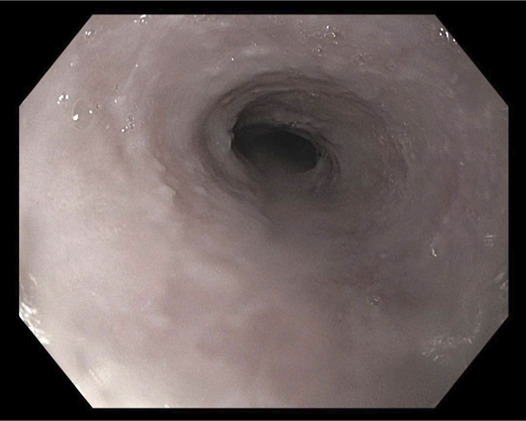

Abstract Image

Lichen planus (LP) is a chronic inflammatory disorder involving the skin and mucous membranes. Esophageal LP is often under-recognized and may present with or without other mucocutaneous sites of involvement. Its diagnosis is made challenging by its variable presentation and high rate of negative biopsies. Although some studies have suggested diagnostic criteria and severity grading, no formal guidelines exist. Diagnosis is made with a combination of clinical presentation, macroscopic findings on endoscopy, and histologic evidence. This case report highlights the challenges in the diagnosis of biopsy-negative esophageal LP and importance of timely diagnosis and initiation of appropriate medical therapy.